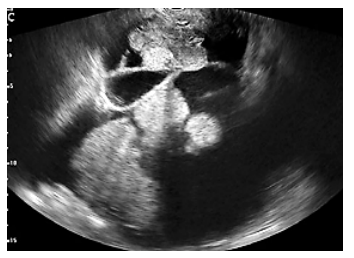

Com uma tumoração com essas características, em ultrassonografia endovaginal de uma mulher com 65 anos de idade é possível fazer a hipótese diagnóstica de